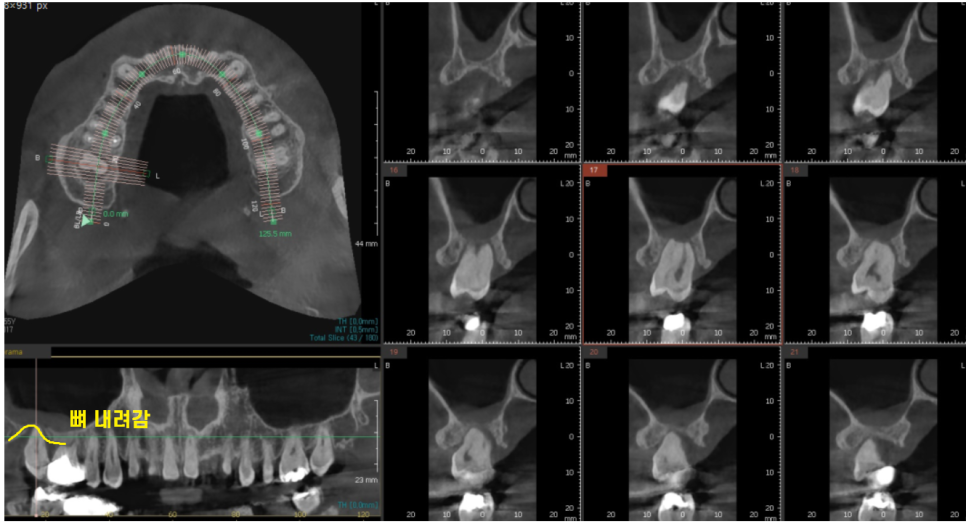

ct속 문제의 치아

뼈가 내려가다못하여

뿌리 염증까지 심해져서

잇몸뼈 내려감

뿌리 염증

2가지 원인으로 잇몸뼈가 많이 없었는데요.

깨끗하게

염증을 제거하고

부족한 뼈를 이식하여 치료를 진행하였습니다.